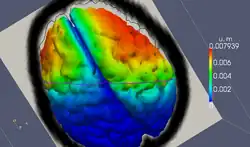

- Computer-assisted surgery

- ACTIVE - Active Constraints Technologies for Ill-defined or Volatile Environments (European FP7 Project)[12][13][14]

{{cite journal}}: Cite journal requires|journal=(help) - ^ "Results - Intraoperative Brain Shift | The Active Project". www.active-fp7.eu.

- ^ "ASL assists neurosurgeons and robots, computes brain deformation in real time - Technology OrgTechnology Org". 14 September 2015.

- ^ "ASL Software Assists Neurosurgeons and Robots". interestingengineering.com. 28 November 2016.